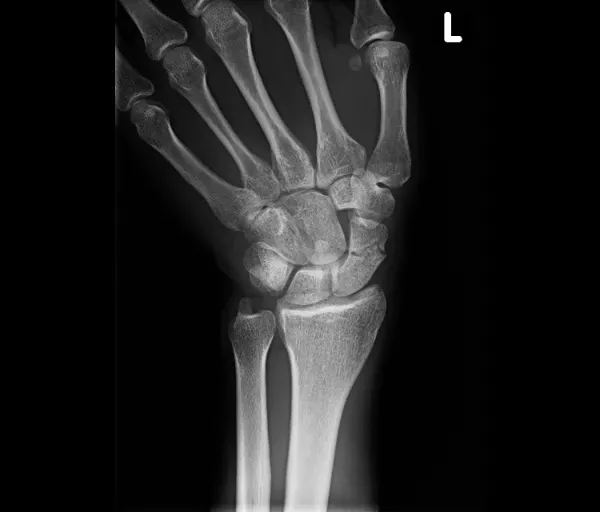

Scaphoidfractuur

Wat is het?

Het scaphoid is een handwortelbeentje aan de duimzijde van de pols. Een breuk ontstaat meestal door een val op de hand. Scaphoidbreuken geven soms weinig klachten, waardoor ze gemakkelijk gemist worden. Het scaphoid heeft een zwakke bloedvoorziening, vooral in de proximale pool. Hierdoor is er risico op:

- non-union/pseudartrose (breuk groeit niet aan elkaar)

- en hierdoor later artrose van de pols (SNAC-wrist)

Klachten

- Pijn aan de duimzijde van de pols

- Soms lichte zwelling

- Moeilijker bewegen van de pols

- Typisch: drukpijn in de anatomische snuifdoos (kuiltje naast de duim wanneer die gestrekt wordt)